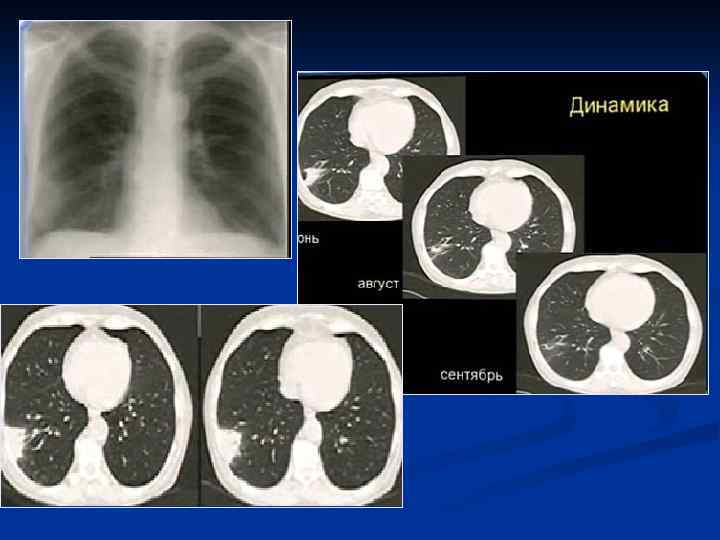

Разрешающаяся пневмония

Показания к КТ грудной клетки n n n Недостаточная диагностическая информация стандартного рентгенологического исследования с наличием клиниколабораторных данных при подозрении на пневмонию Стертые клинические и лабораторные данные у больных с подозрением на пневмонию Затянувшийся кашель, субфебрилитет у больных с ОРВЗ Обострения хронических заболеваний бронхо-легочной системы Осложнения в процессе лечения больных пневмонией Затянувшиеся пневмонии

Пневмония S 6 левого легкого

Протокол - в S 6 левого легкого выявляется инфильтрация легочной ткани смешанного характера, на фоне которой прослеживаются просанты бронхов, занимающая сегмент, контактирующая с плеврой - усилен сосудистый рисунок в правом легком - утолщена плевра по ходу косой междодевой щели - корни реактивны - диафрагма расположена обычно Заключение: Рентгенологические признаки пневмонии S 6 левого легкого